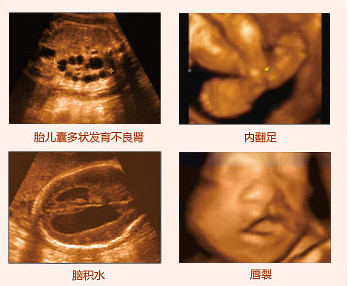

在四維彩超胎兒篩畸檢查中,首先要篩查的是頭顱畸形,看胎兒是否是無腦兒、腦積水、小頭畸形。如果早四維彩超檢查中,發(fā)現胎兒發(fā)育存在異常,可以對有嚴重畸形的胎兒在產前做出診斷,對發(fā)現有輕微異?;蚩梢僧惓5奶海山o予密切追蹤觀察,為臨床提前干預、早期處理提供建議。推選閱讀 四維彩超對肚中寶寶會有影響嗎

據醫(yī)生介紹,較易致胎兒畸形的外因有病毒、射線、 物等,內因則與遺傳因素或染色體的異常有關。而同其它超聲診斷過程相比,四維彩超可以實時的觀察人體內部器官的動態(tài)運動。臨床醫(yī)生和超聲科醫(yī)生可以檢測和發(fā)現各種異常,從血管畸形到遺傳性綜合征。四維彩超能夠多方位、多角度地觀察宮內胎兒的生長發(fā)育情況,為早期診斷胎兒先天性體表畸形和先天性心臟疾病提供準確的科學依據,以便盡早發(fā)現寶寶是否存在這樣的不良情況,能使媽媽生個聰明健康的小寶寶。推選閱讀 傳統b超胎兒產后畸形 莆田盛興醫(yī)院四維彩超成較

因為畸形兒對大多數家庭來說都難以接受這個事實,令親人難以相信,而且這種情況越早進行干預對孕婦的身體以及家屬的心理影響會越小。而四維彩超作為目前上進的彩色超聲檢查設備,具備較強大的排畸功能,對胎兒大體的畸形:如唇裂、腭裂、骨骼發(fā)育異常等能早期診斷。莆田盛興醫(yī)院引進美囯先進的GE四維彩色超聲設備,是莆田準媽媽做好胎兒排畸較關鍵的一步。